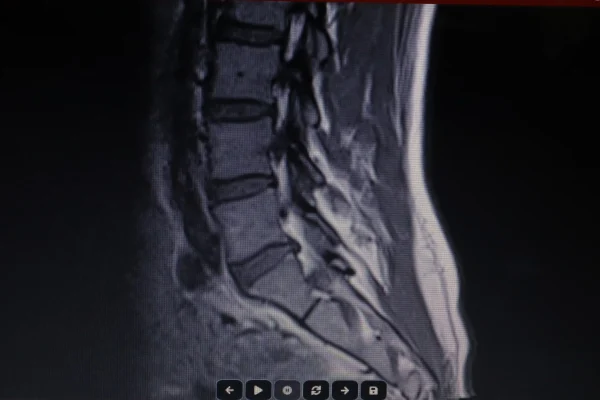

Extrusão Discal: o que é, sintomas, diagnóstico e tratamento da hérnia de disco extrusa

Extrusão discal é uma forma avançada de hérnia de disco em que o material interno do disco rompe completamente sua camada externa e se projeta para fora, podendo comprimir nervos da coluna e causar dor irradiada, formigamento e fraqueza muscular. Para entender por que essa condição merece atenção especial, é preciso conhecer como a coluna […]